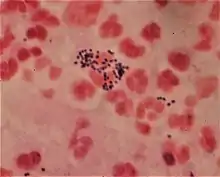

Gram staining differentiates bacteria by the chemical and physical properties of their cell walls. Gram-positive cells have a thick layer of peptidoglycan in the cell wall that retains the primary stain, crystal violet. Gram-negative cells have a thinner peptidoglycan layer that allows the crystal violet to wash out on addition of ethanol. They are stained pink or red by the counterstain,[3] commonly safranin or fuchsine. Lugol's iodine solution is always added after addition of crystal violet to strengthen the bonds of the stain with the cell membrane.

Gram-positive bacteria have a thick mesh-like cell wall made of peptidoglycan (50–90% of cell envelope), and as a result are stained purple by crystal violet, whereas gram-negative bacteria have a thinner layer (10% of cell envelope), so do not retain the purple stain and are counter-stained pink by safranin. There are four basic steps of the Gram stain:

After decolorization, the gram-positive cell remains purple and the gram-negative cell loses its purple color.[17] Counterstain, which is usually positively charged safranin or basic fuchsine, is applied last to give decolorized gram-negative bacteria a pink or red color.[3][18] Both gram-positive bacteria and gram-negative bacteria pick up the counterstain. The counterstain, however, is unseen on gram-positive bacteria because of the darker crystal violet stain.